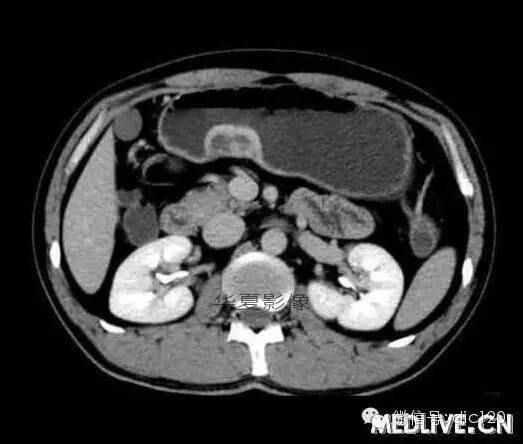

男,36歲,間斷性返酸噯氣3年,3個月前出現(xiàn)上腹疼痛,饑餓時加重。圖1-3為CT平掃,圖4-6分別為CT增強(qiáng)掃描的動脈期、門脈期和延遲期。

CT檢查可見胃幽門前區(qū)胃小彎側(cè)胃壁局限性增厚、隆起或伴凸向胃腔內(nèi)的小結(jié)節(jié)灶,寬基地,境界光整,注射對比劑,增強(qiáng)掃描后,CT值可達(dá)50HU以上,與正常胰腺強(qiáng)化相仿。

胃迷走胰腺大多位在距幽門1-6cm的胃竇胃大彎側(cè),粘膜下層內(nèi),為1-3cm大小的病灶。 與胃壁以寬基底相,增強(qiáng)掃描病灶表面覆蓋的黏膜明顯強(qiáng)化且連續(xù),病灶內(nèi)無明顯壞死,病變強(qiáng)化方式類似于正常胰腺組織;當(dāng)病灶出現(xiàn)邊緣臍凹征或中央導(dǎo)管征時,對EP的診斷具有一定的特異性。